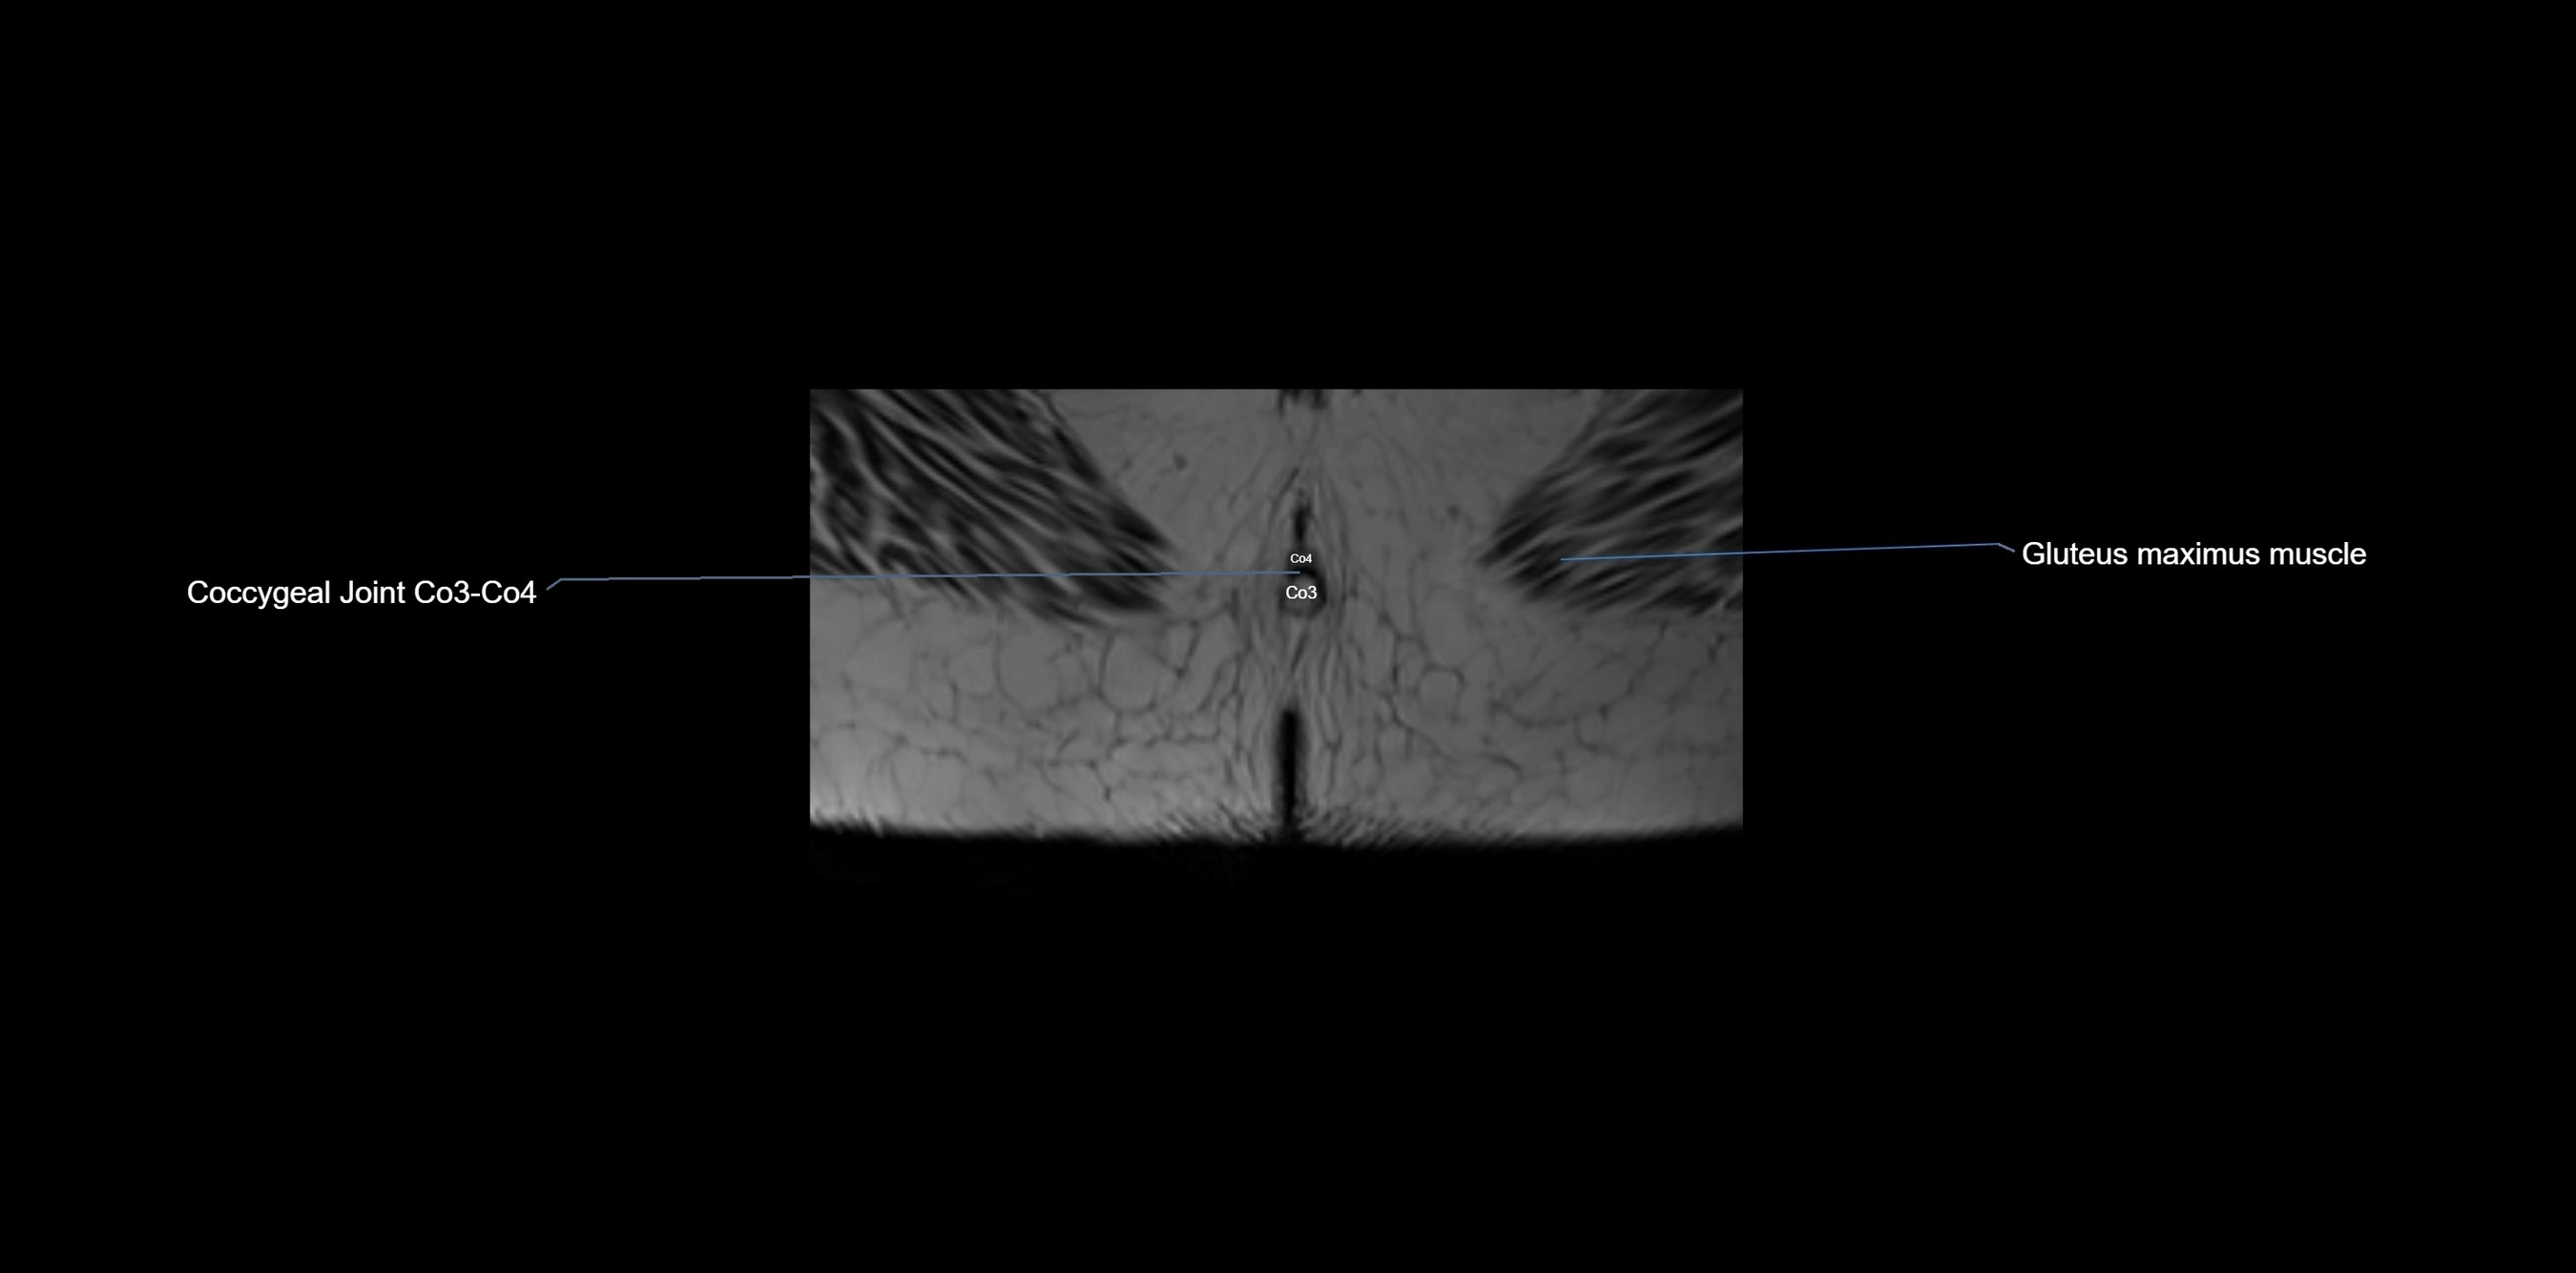

MRI Appearance

T1-weighted images:

• Cortical bone appears very low signal (dark); marrow shows intermediate signal

• Iliac fossa fat is bright against low-signal cortex

T2-weighted images:

• Cortical bone remains dark

• Marrow signal varies depending on fat content; edema or tumor shows hyperintensity

STIR:

• Suppresses fat, making bone marrow edema, fractures, or infiltrative lesions appear bright

• Excellent for trauma, sacroiliitis, and metastatic evaluation

T1 Fat-Saturated (Pre-contrast):

• Marrow: intermediate signal, fat suppressed

• Useful for detecting subtle marrow abnormalities adjacent to iliac cortex

T1 Fat-Saturated Post-Contrast (Gadolinium):

• Enhances vascularized structures, marrow pathology, tumors, and inflammatory changes

• Highlights soft tissue or bone invasion in pelvic neoplasms

MRI Non-Contrast 3D Imaging:

• Provides 3D morphology of iliac wing, crest, and articulations

• Used in preoperative planning for pelvic surgery and trauma reconstruction